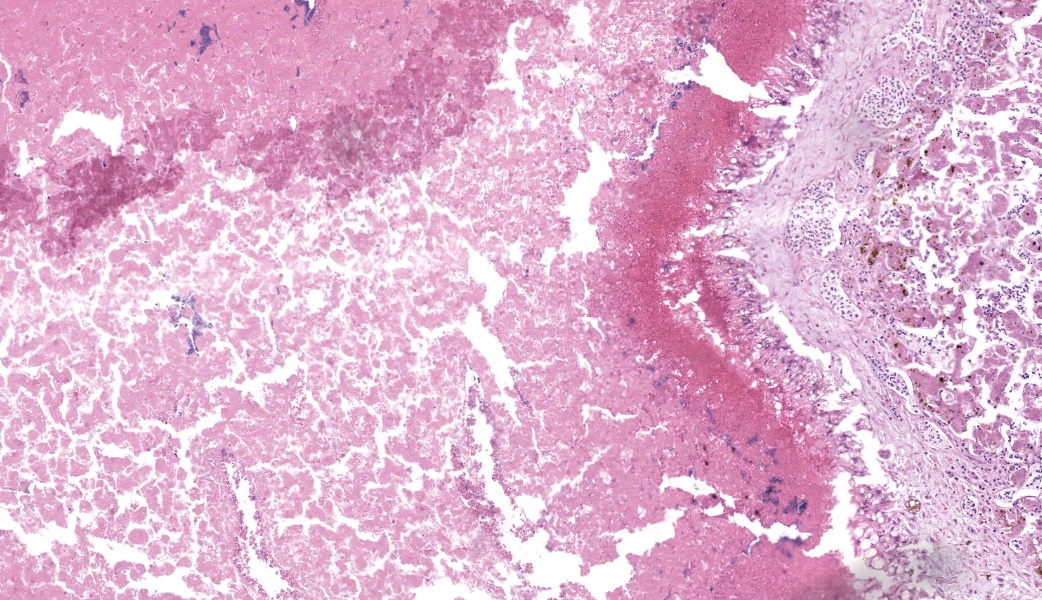

Microscopic Description:

Liver: Three sections of liver are examined. Within one section, there are multiple and coalescent, irregularly shaped granulomas replacing up to 60% of the tissue, multifocally blending in with the fibrous connective tissue of portal areas. Granulomas center around hypereosinophilic necrotic material mixed with relatively low to medium numbers of degenerate heterophils and cellular debris and multiple clusters of coccoid bacteria. Bordering the necrotic center is a layer of palisading macrophages with abundant eosinophilic and frequently vacuolated cytoplasm (epithelioid macrophages) and occasional multinucleated giant cells, which are further outlined by a robust layer of fibroblasts and collagen. Portal areas are variably expanded by medium to high numbers of lymphocytes, plasma cells, macrophages, including many laden with brown cytoplasmic granules, intermingled with numerous bile ducts (biliary hyperplasia), which extend into the adjacent parenchyma. In some portal areas, there are higher numbers of granulocytes with large, indented, vesiculate nuclei (interpreted as myeloid precursor cells and extramedullary hematopoiesis). Throughout all three sections of liver are individual necrotic hepatocytes to large regions of coagulative necrosis often centered around centrilobular veins, characterized by hepatocytes with shrunken, angular cell borders, hypereosinophilic cytoplasm and a pyknotic to karyorrhectic nucleus; larger areas of coagulative necrosis are frequently infiltrated by viable and non-viable heterophils. Within areas of necrosis and areas of viable hepatocytes are small clusters of coccoid bacteria within sinusoids.Spleen: The splenic parenchyma is interrupted by a few, relatively smaller, coalescing granulomas centered around numerous viable and non-viable heterophils, pyknotic nuclei and cellular and karyorrhectic debris, which is separated by a collar of collagen and macrophages with the occasional multinucleated giant cells. Within these regions, there are multifocal cocci bacteria colonies. There are deposits of fibrin and serum protein present throughout the sinuses and around ellipsoids. Within these foci are few reticuloendothelial cells, red cells, low numbers of lymphocytes and macrophages, as well as pyknotic nuclei and karyorrhectic and cellular debris and colonies of coccoid bacteria.

Liver: granulomatous and necrotizing hepatitis, multifocal to coalescing, severe, with intralesional cocci and biliary hyperplasiaSpleen: granulomas, multifocal, marked, with intralesional and embolic cocci

- Liver: Hepatitis, necrotizing, heterophilic and granulomatous, chronic, multifocal to coalescing, severe, with numerous cocci.

- Spleen: Splenitis, necrotizing, heterophilic and granulomatous, chronic, multifocal, moderate, with numerous cocci.

The University of Pennsylvania's Dr. Nathan Helgert moderated this year's 11th conference. This is his first time moderating for the WSC, and participants thoroughly enjoyed his quick wit and engaged teaching style. He chose to focus on poultry and ruminant pathology, which participants are always grateful for. This first case was a classic entity with fantastic histologic lesions that, according to some conference goers, provided the perfect moment to make use of the term "geographic" to describe those dramatic areas of necrosis. They truly resemble some beautiful cartography.Conference discussion focused on the diagnostic approach to cases like this one where additional diagnostics are required to "suss out" the etiologic agent. Participants were asked to take a figurative step back and develop a list of possible causes of bacterial sepsis in chickens that could lead to hepatic and splenic lesions like these. The list included E. coli (colibacillosis), Salmonella typhimurium, Staphylococcus aureus, Enterococcus spp, Streptococcus spp.,Erysipelothrix rhusiopathiae (although this is more likely in turkeys and pheasants than in chickens), Mycobacterium spp (especially M. avium), and Pasteurella multocida, to name just a few. Some of these look nearly identical to one another both grossly and histologically, while others of these have more distinct features. Either way, culture and special stains will be needed.